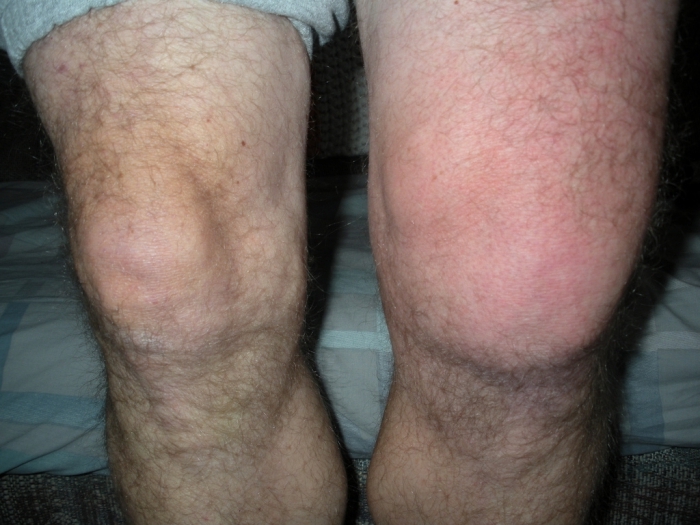

Образование отечности

Отечность коленного сустава образовывается вследствие чрезмерной выработки синовиальной жидкости. Как правило, отек возникает через несколько дней после травмы.